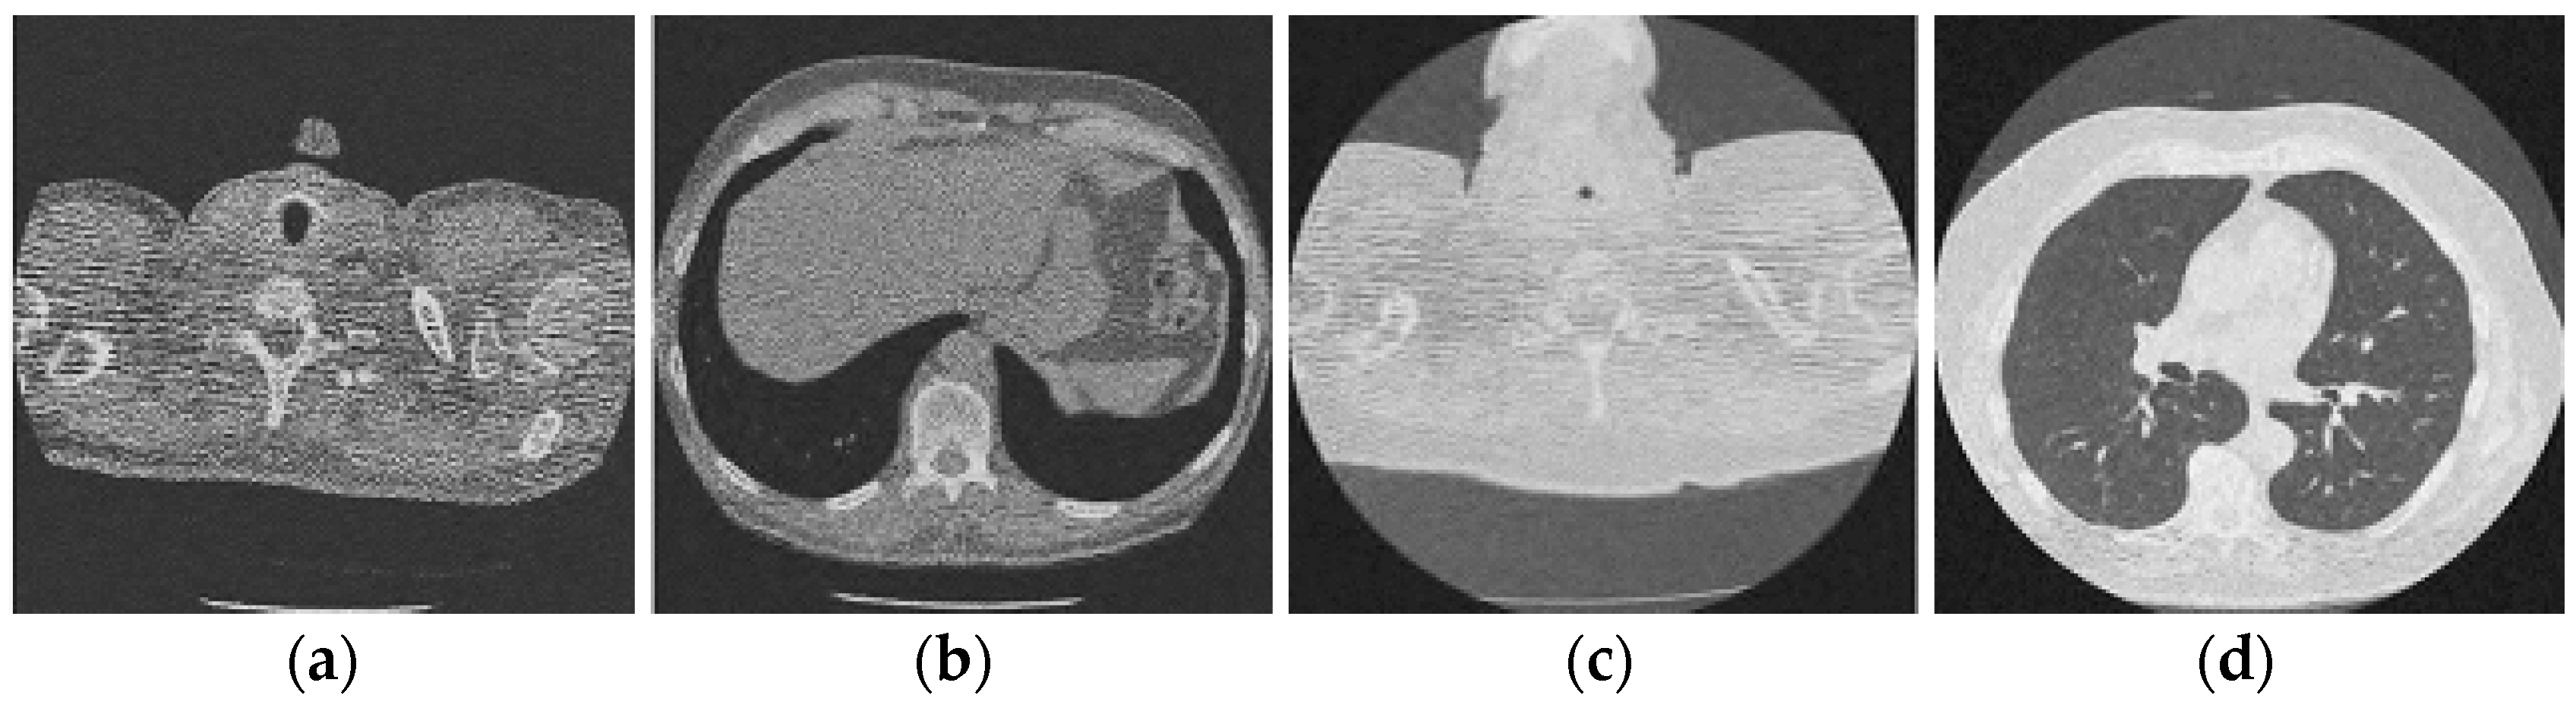

Figure 11.

Results of the proposed CT image denoising method; (a) Denoised CT1 image; (b) Denoised CT2 image; (c) Denoised CT3 image; (d) Denoised CT4 image.

For effective comparison to other systems available out there, this system has been pitted against seven of the most robust and widely used denoising techniques out there, i.e., Figure 4, Figure 5, Figure 6, Figure 7, Figure 8, Figure 9, Figure 10 and Figure 11. All the denoising frameworks performed reasonably well, with similar levels of denoising in their outputs, within a certain margin of error and variations. The result from these techniques for four CT images is displayed in Figure 4, Figure 5, Figure 6, Figure 7, Figure 8, Figure 9, Figure 10 and Figure 11. The CT image manipulation gave rise to redundant overcorrection, cumulating in distortion of the black borders and the introduction of fuzziness. Only two CT images from the rivaling systems have managed to preserve the blackness of the outer borders in the CT images. The result from [45] in Figure 9c is the least clear, with distortion visible to the unaided observer. A similar problem is observed in Figure 4a,c, where the system overcorrects, introducing more distortion instead of improving clarity. Figure 10d comes closest to the original, though the proposed framework is superior, as illustrated in the next section. From Figure 11a–d, it is very clear that the proposed algorithm gives better outcomes in comparison to existing methods in terms of clinical features, such as edges, textures, contrasts, and brightness.